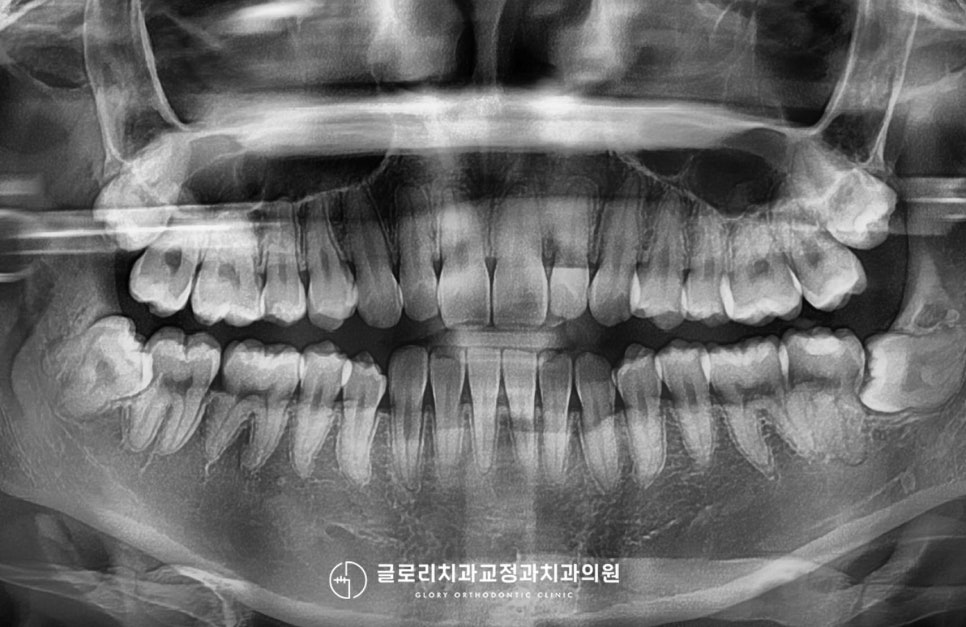

문제점부터 하나씩 차근차근 살펴보면,

윗니 전치부의 가운데의 인접치로 측절치가

유독 이동한 모습이 눈에 띄었습니다.

현재 하악 전치부 뒤쪽으로는

장치를 부착해 재발이 되는 것은

어느 정도 막았지만,

윗니는 이미 틀어진지 오래라

새로운 치료 방법을 찾아야 될 때인데요.